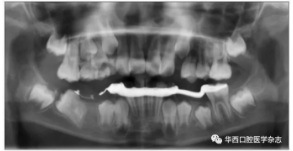

全景片及錐形束CT(cone beam computed tomo-graphy,CBCT)三維重建影像顯示:46牙胚存在,牙冠朝向遠中,且牙長軸與下頜骨下緣接近平行,遠中根發(fā)育約為根長2/3,近中根發(fā)育約為根長1/2且稍向下彎曲,近中根與45牙關系密切,下頜其余牙胚正常(圖2、圖3)。